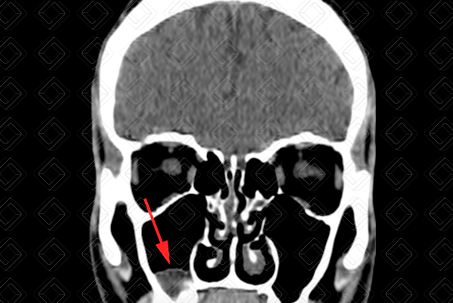

Texto alternativo para a imagem Figura 2. Créditos: Dra. Elazir Mota - Rio de Janeiro/RJ

Texto alternativo para a imagem Figura 3. Créditos: Dra. Elazir Mota - Rio de Janeiro/RJ

Descrição das figuras 2 e 3: Ressonância magnética da face, imagens ponderadas em T2, reconstruções axial e coronal, evidenciando imagem no assoalho do seio maxilar esquerdo, com sinal elevado em T2 (seta amarela).

• Ressonância magnética da face (figuras 2 e 3): Imagem também de contornos lobulados, com sinal variável nas imagens ponderadas em T1 (depende do conteúdo proteico) e alto sinal em T2 .